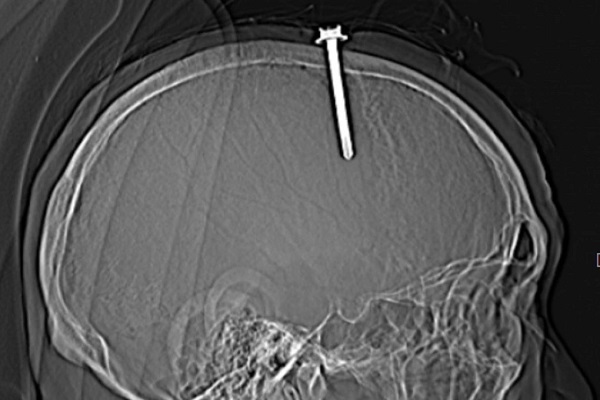

北中部地方タインホア省総合病院は17日、5cmのねじを頭に打ち込んだ患者を救う手術を行ったことを発表した。

L・Q・Tさん(男性・63歳)は、ねじが頭蓋骨を貫通し、脳に深く刺さっている状態で病院に運び込まれた。

家族によると、Tさんはうつ病にかかっており、不眠症に悩まされ、体に痛みや不快感を感じていた。その痛みに耐えかねて、Tさんは自ら頭頂部にねじを打ち込む行為に及んだが、家族が即座に発見し、病院に緊急搬送した。

頭蓋骨に直径0.5cm、長さ5cmのねじが刺さっており、医師らは早急に異物を除去する手術を行わない場合、患者が死亡するリスクが高いと判断。2時間あまりにわたって手術を行い、患者の頭部から5cmのねじを取り除いた。

数日間の治療と経過観察の後、患者の健康状態は回復したため、退院し、自宅で治療を続けることが許可された。